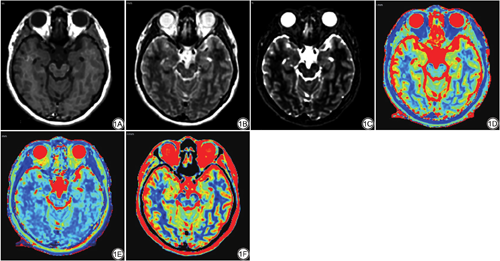

将SyMRI的扫描数据导入SyMRI后处理软件(v11.2.2,SyntheticMR公司),自动计算得到T1、T2和PD图谱(图1)。使用dcm2nii软件将T1、T2、PD和3D T1WI-SPGR扫描数据转换成NIFTI格式。随后采用FSL软件(https://fsl.fmrib.ox.ac.uk/fsl/fslwiki/FSL)将T1、T2和PD图谱配准到标准脑空间(MNI)。最后使用AAL模版提取海马体的定量参数值。